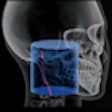

Subtraction method tracks implant bone loss